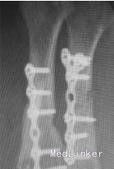

入院诊断左手损伤,左第2~5掌骨开放性粉碎性骨折,左第2~5指伸肌撕脱损伤,左手背软组织挫裂伤伴缺损,左中、小指指深屈肌腱断裂,左环指指深屈肌腱撕脱损伤,左手骨间肌、蚓状肌断裂、挫裂伤,左手指掌侧总神经、指背侧总神经及指神经断裂,左手指掌指总动静脉、掌浅弓、掌深弓断裂,左手掌软组织挫裂伤,左大小鱼际肌部分断裂,左桡骨下段横形骨折,左肘部软组织损伤。入院后给予急诊清创固定1周后左小指、环指缺血坏死,再次手术行左环、小指切除,左第5掌骨切除、左第4掌骨残端修整、左桡骨下端切开复位固定术,左第2、3掌骨骨折端术后5个月无愈合迹象。术后X线片提示:骨折断端存在间隙,骨痂很少或无,断端分离,髓腔封闭,骨质疏松,无骨小梁形成,符合骨折不愈合诊断。

该患者骨折不愈合处获得完全骨性愈合,临床愈合时间2个月。治疗过程中未出现针孔及深部感染。